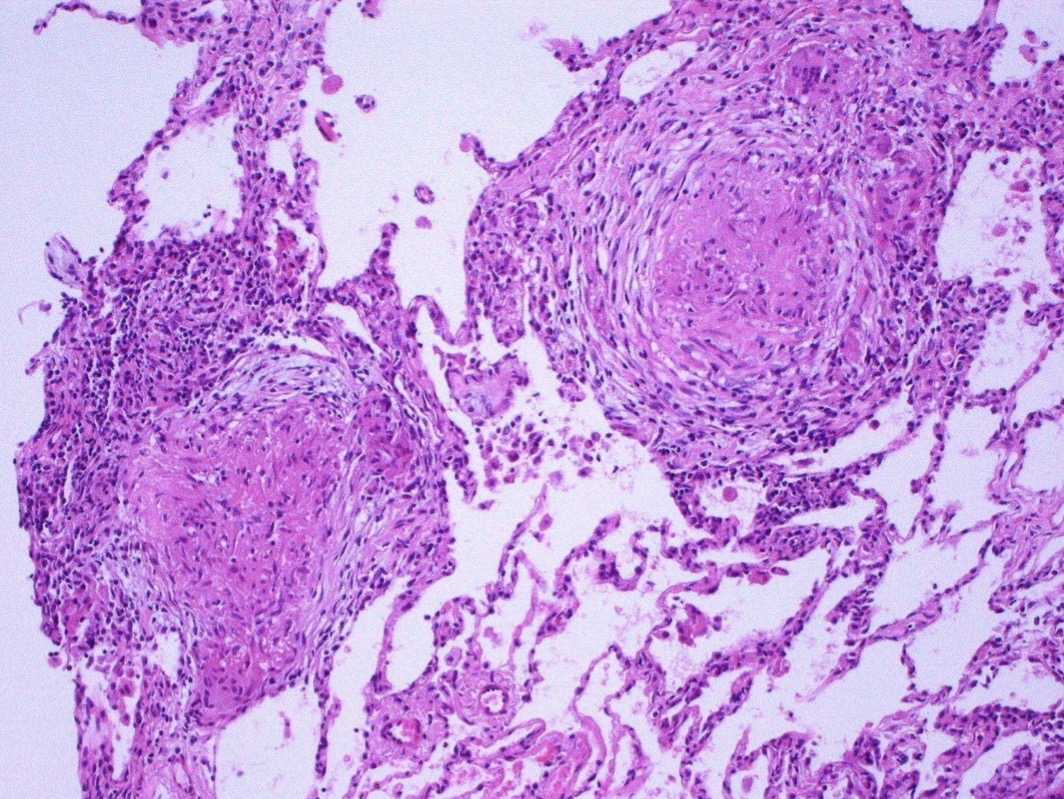

B- describe

A- Granulomatous inflammation

B-Tow pulmonary granulomas , Consists of epithelioid cells, giant cells, lymphocytes, plasma cells, and fibroblasts.

A- identify

A- typical Tuberculosis Granuloma

B- area of central necrosis surrounded by multiple langhan type giant cells , epithelioid cells , lymphocyte

C- identify the marked structure

A- Caseating granuloma

B-Central area of necrosis (appears pink, amorphous, and irregular) Surrounded by epithelioid cells.

C- area of Necrosis